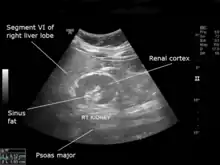

| An ultrasound scan of a hypoplastic right kidney in an adult male. | |